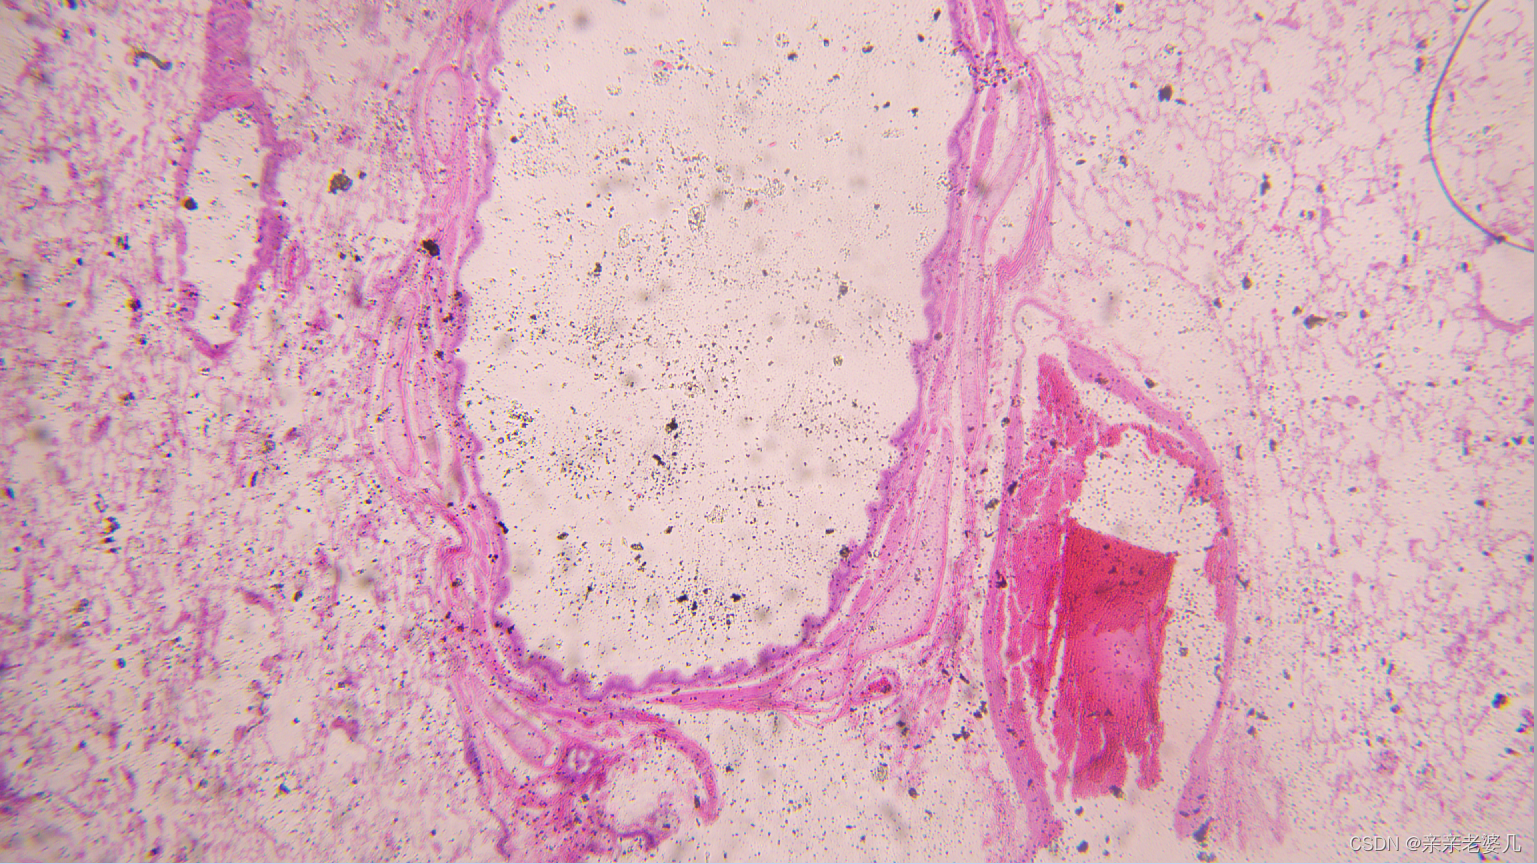

9. 千奇百怪的疾病——疾病的显微诊断及大体实物标本展示

如何获得标本:

手术 取材 包埋 蜡块 切片 染色

肺水肿

正常肺